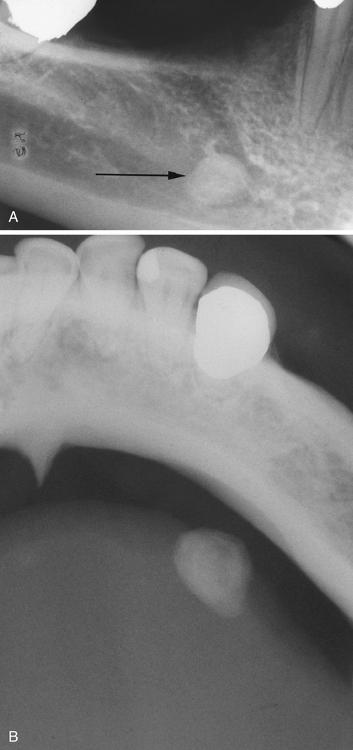

Blue-pigmented nodule on the lower lip. There is often a bluish translucent hue to the swelling, although deeper lesions may be normal in color.

mucocele

Nodule on the posterior buccal mucosa. The reported duration of the lesion can vary from a few days to several years; most patients report several weeks.

mucocele

Exophytic lesion on the anterior ventral tongue from the glands of Blandin-Nuhn. The lower lip is by far the most common site for this type of lesion.

mucocele

Vesicle-like lesion on the soft palate. The pathologist must be aware of this lesion and should not mistake it microscopically for a vesiculobullous disorder.

superficial mucocele